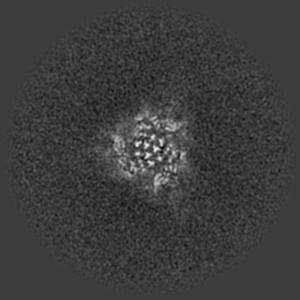

SARS-CoV-2 Wuhan Spike ectodomain in complex with human polyclonal antibody ModWu-NTD3 (mRNA-1273 vaccine)

Single-particle3.4 Å

Sample: SARS-CoV-2 Wuhan spike ectodomain in complex with human polyclonal antibody ModWu-NTD3